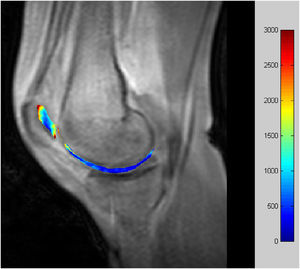

De las imágenes seriadas obtenidas rápidamente tras administrar un medio de contraste en bolo se analiza el comportamiento de la captación tisular a partir de la entrada arterial. Mediante cálculos y ajustes matemáticos se obtienen los parámetros farmacocinéticos tisulares de la permeabilidad vascular desde el vaso (Ktrans) (fig. 3), la fracción de volumen de intercambio del intersticio (ve), el coeficiente de extracción del intersticio al vaso y la fracción de volumen sanguíneo intercambiable.

Hay estudios que demuestran la relación entre el aumento de estos parámetros y un mayor grado de degeneración del cartílago articular. Así, se ha demostrado que hay diferencias estadísticamente significativas entre el cartílago normal, la condromalacia y la artrosis para Ktrans y ve, con aumentos muy significativos conforme la enfermedad progresa (fig. 4). Los valores son, además, reproducibles con valores de variación inferiores al 15% para equipos de 1,5 T10 e incluso menores para equipos de mayor intensidad de campo11.